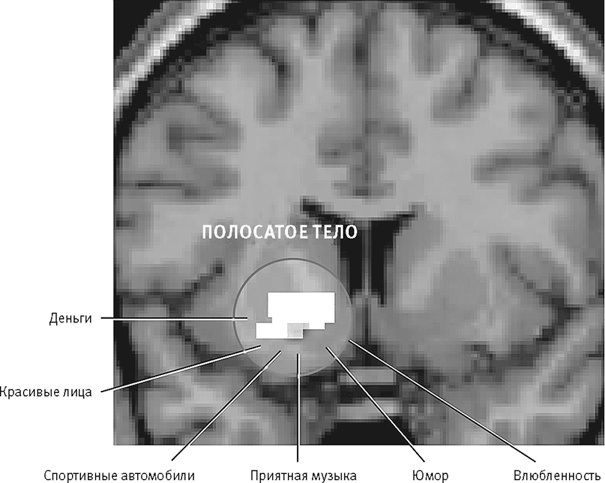

Как можно было предположить, вещества, усиливающие или продлевающие естественное действие дофамина, приносят нам большее удовольствие. Зависимость, вызываемая рядом психотропных веществ, например кокаином или амфетамином, связана именно с тем, что они сбивают с толку дофаминергическую систему, заставляя мозг думать, будто он получает награду, хотя никакой награды нет (рис. 26–4).

Рис. 26–4. Дофаминергические нейроны полосатого тела реагируют на всевозможные стимулы, доставляющие нам удовольствие.